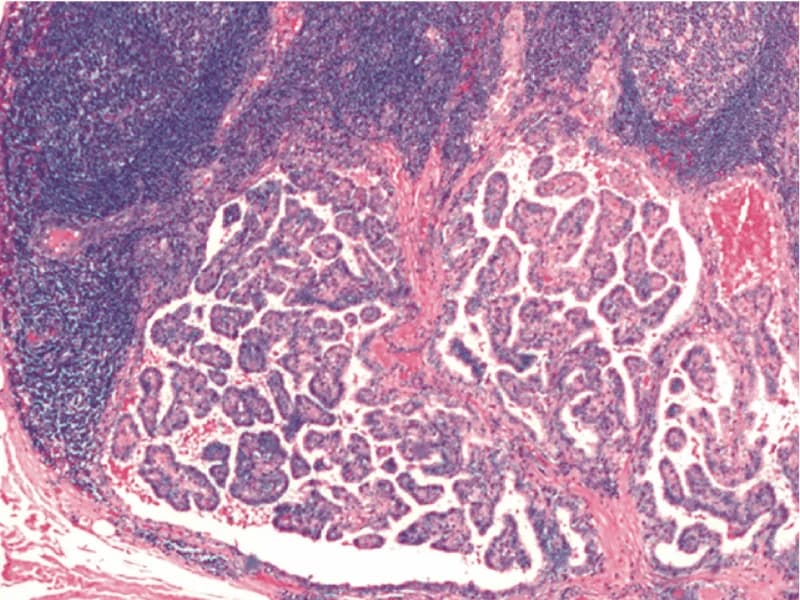

Carcinoma papilífero

É o mais comum, responsável por 95% dos casos, e a maioria de tudo o que você lê sobre câncer de tireoide é sobre ele. Tem altas taxas de cura, 95% em 30 anos. Não existe fator causal conhecido. Ninguém sabe por que ele surge nem você tem culpa de adquiri-lo.